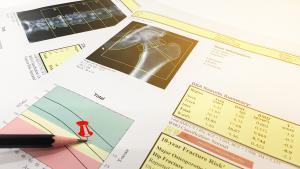

La consecuencia silenciosa de la menopausia que solo da la cara cuando rompe

¿Se puede prevenir la osteoporosis provocada por el tratamiento del cáncer de mama?

Rebeca Gil 22/09/2023 - 13:51 CEST 0 Comentarios